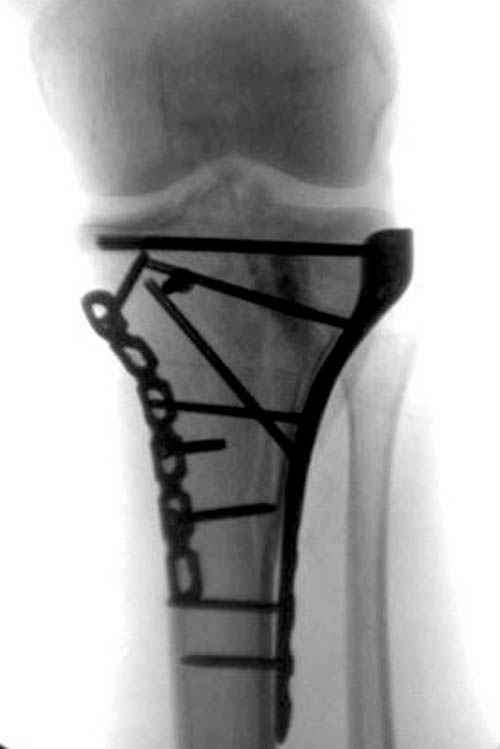

АЛ> Интересует срок проведения оперативного вмешательства,

АЛ> оптимальный выбор фиксатора (особенно интересует возможность БИОС

Интрамедуллярный остеосинтез диафизарного перелома тут возможен, но в первую очередь надо с помощью КТ уточнить повреждение суставного конца. Импрессионный перелом наружного мыщелка явный есть, может, и медиальная колонна повреждена, так что надо в первую очередь планировать открытую репозицию с замещением дефекта с фиксацией пластиной или аппаратом. Если получается технически, можно поверх уже синтезированного стержнем диафиза.

Уважаемый Александр Николаевич! Прошу прощения за некачественные сканы. КТ вообще-то реально, но сложности с транспортировкой больного в соседний корпус (такая перевозка и перекладывание для больных - дополнительная травма). По Р-граммам медиальный отдел вроде целый, но наружный мыщелок "отклячен" и суставная поверхность явно просела. У нас весь вопрос в методе фиксации или же их сочетании - одна пластина, опорная пластина и стержень (я так понял, что вы предлагаете сначала фиксировать диафиз, а потом заняться мыщелком?), винты и стержень, аппарат...Опять же состояние м/тканей (плотный отек, кровоизлияние)...

Пациенту сделали КТ - ухитрились сделать на шине Белера (не давал положить прямую ногу) - срезали передний отдел. Планируется на пятницу (24.12) на операцию - синтез длинной мыщелковой LCP-пластиной Synthes :). Отек ближе к слову умеренный (окружность голени +4 см по сравнению со здоровой). КТ и снимок на вытяжении прилагаются.